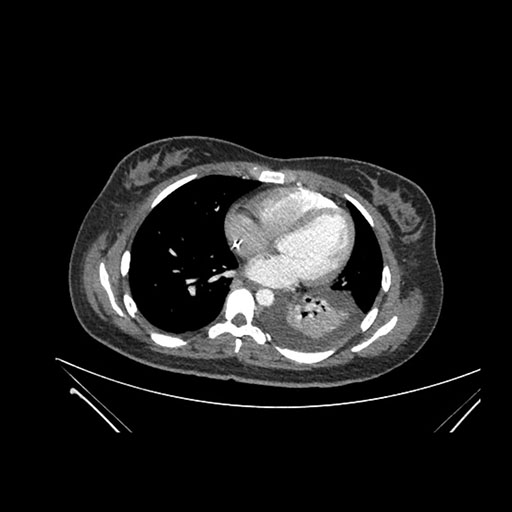

Axial Arterial

Axial Venous